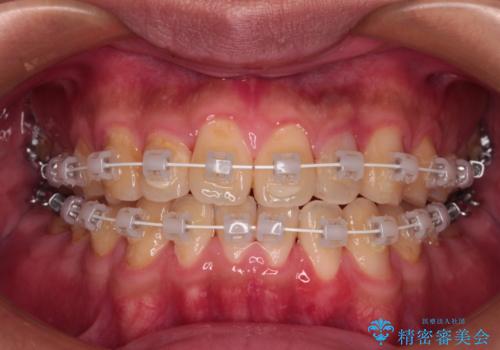

- 審美装置

クロスバイトはありましたが、叢生の程度としては酷くなかったため、ワイヤー矯正でもマウスピース矯正でも、好きな方を選択していただきました。

一日中マウスピースを装着する煩わしさから、マウスピース矯正を継続する自信がないとのことで、ワイヤー装置にて矯正治療を行うこととしました。